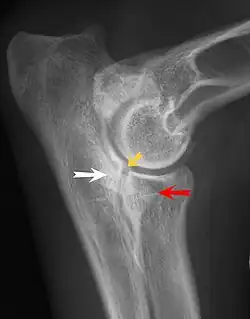

Most primary lesions are related to osteochondrosis, a disease of the joint cartilage, and osteochondritis dissecans (OCD), the separation of a flap of cartilage on the joint surface. Other common causes of elbow dysplasia include an ununited anconeal process (UAP) and fragmented or ununited medial coronoid process (FCP or FMCP).[1]

In OCD, the normal change of cartilage to bone in the development of the joint fails or is delayed. The cartilage continues to grow and may split or become necrotic. The cause is uncertain, but possibly includes genetics, trauma, and nutrition (including excessive calcium and decreased vitamin C intake).[4] OCD lesions found in the elbow at the medial epicondyle of the humerus are caused by disturbed endochondral fusion of the epiphysis of the medial epicondyle with the distal end of the humerus, which may in turn be caused by avulsion of the epiphysis.[5] Specific conditions related to OCD include fragmentation of the medial coronoid process of the ulna (FMCP) and an ununited anconeal process of the ulna (UAP). All types of OCD of the elbow are most typically found in large breed dogs, with symptoms starting between the ages of 4 and 8 months.[4] Males are affected twice as often as females. The disease often affects both elbows (30 to 70 percent of the time), and symptoms include intermittent lameness, joint swelling, and external rotation and abduction of the paw.[6] Osteoarthritis will develop later in most cases.

UAP is caused by a separation from the ulna of the ossification center of the anconeal process.[7] FMCP is caused by a failure of the coronoid process to unite with the ulna.